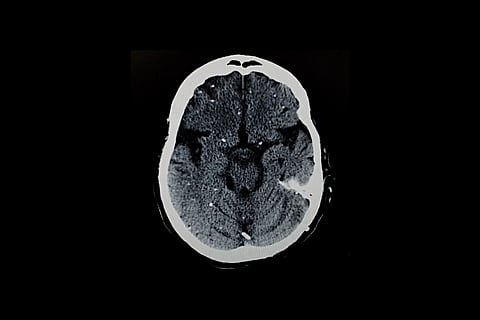

Se protege formando pequeños quistes, principalmente en el cerebro y los músculos. Cada quiste puede albergar cientos de parásitos latentes.

Estos parásitos pueden despertar más tarde, especialmente en personas con sistemas inmunitarios débiles, lo que a veces puede provocar graves problemas cerebrales o oculares. La infección durante el embarazo también puede dañar al feto en desarrollo.

Estos quistes se encuentran con mayor frecuencia en neuronas, células que conforman el sistema nervioso. Pero también aparecen en el corazón y el músculo esquelético, lo que ayuda a explicar por qué las personas pueden infectarse al comer carne poco cocinada.

Estos pueden propagarse por el cuerpo y causar enfermedades graves como daño cerebral (encefalitis toxoplásmica) o pérdida de visión (toxoplasmosis retiniana).